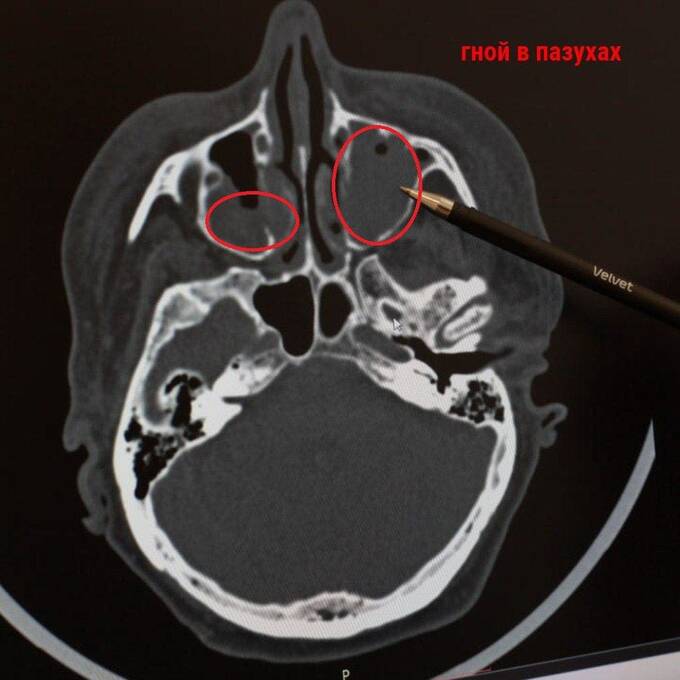

В местную больницу поступила 66-летняя Ирина (имя изменено). Её лицо было настолько отёкшим, что женщина не могла открыть глаза. Всему виной флегмона глазниц – острое гнойное воспаление, вызванное невылеченным насморком.

Гной заполнил пазухи и окологлазничные области пациентки - по словам врачей, женщина могла умереть из-за развития сепсиса и тромбоза.

«Мы сделали пункцию и дренировали пазухи и флегмоны глазниц. Затем провели операцию по вскрытию и удалению содержимого верхнечелюстной пазухи, именно от неё пошёл весь воспалительный процесс. Операция прошла успешно», – рассказал Евгений Брандман.